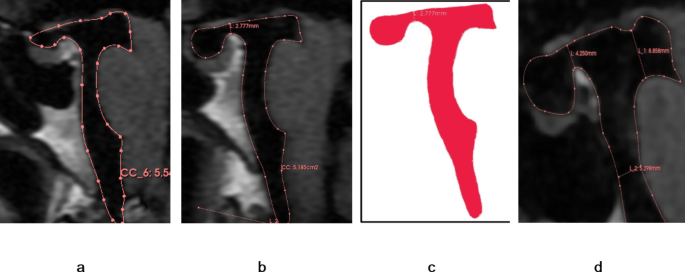

Measurements were conducted systematically in the following steps. First, DICOM-formatted images were imported into the 3D Slicer software and the “Markups” function was used to delineate the approximate shape of the cerebral aqueduct on the “OSag 3D-FIESTA” sequence images (Fig. 1a). The diameters at the opening of the third ventricle, the site of stenosis (typically located 3–4 mm from the surface of the cardiac apex), and the opening of the fourth ventricle (Fig. 1b) were measured. Concurrently, the “Link slice views” feature of 3D Slicer was used to automatically align the “OSag 3D-FIESTA” sequence images with the axial plane images, where the diameter of the cerebral aqueduct was measured again on the axial images (Fig. 1c), ensuring that the measurements obtained in the sagittal and axial planes were consistent. Then, the length of the cerebral aqueduct was measured on the “Sag 3D-FIESTA” sequence images (Fig. 1d). Finally, the angle between the anterior-superior segment and the posterior-inferior segment of the cerebral aqueduct was measured (Fig. 1e).

Analysis of mesencephalic aqueduct morphology on magnetic resonance images of the brainstem. (a) Borders of the mesencephalic aqueduct in the mid-sagittal plane. (b) Diameters of the mesencephalic aqueduct at the rostral opening with the third ventricle, constriction, and termination at the fourth ventricle. (c) Measurement of these same aqueduct diameters in the axial plane using the automatic linkage feature of 3D Slicer. (d) Length of the mesencephalic aqueduct. (e) Angle between the anterior upper and posterior lower segments of the mesencephalic aqueduct. Segments are separated by the constriction (as shown in b).